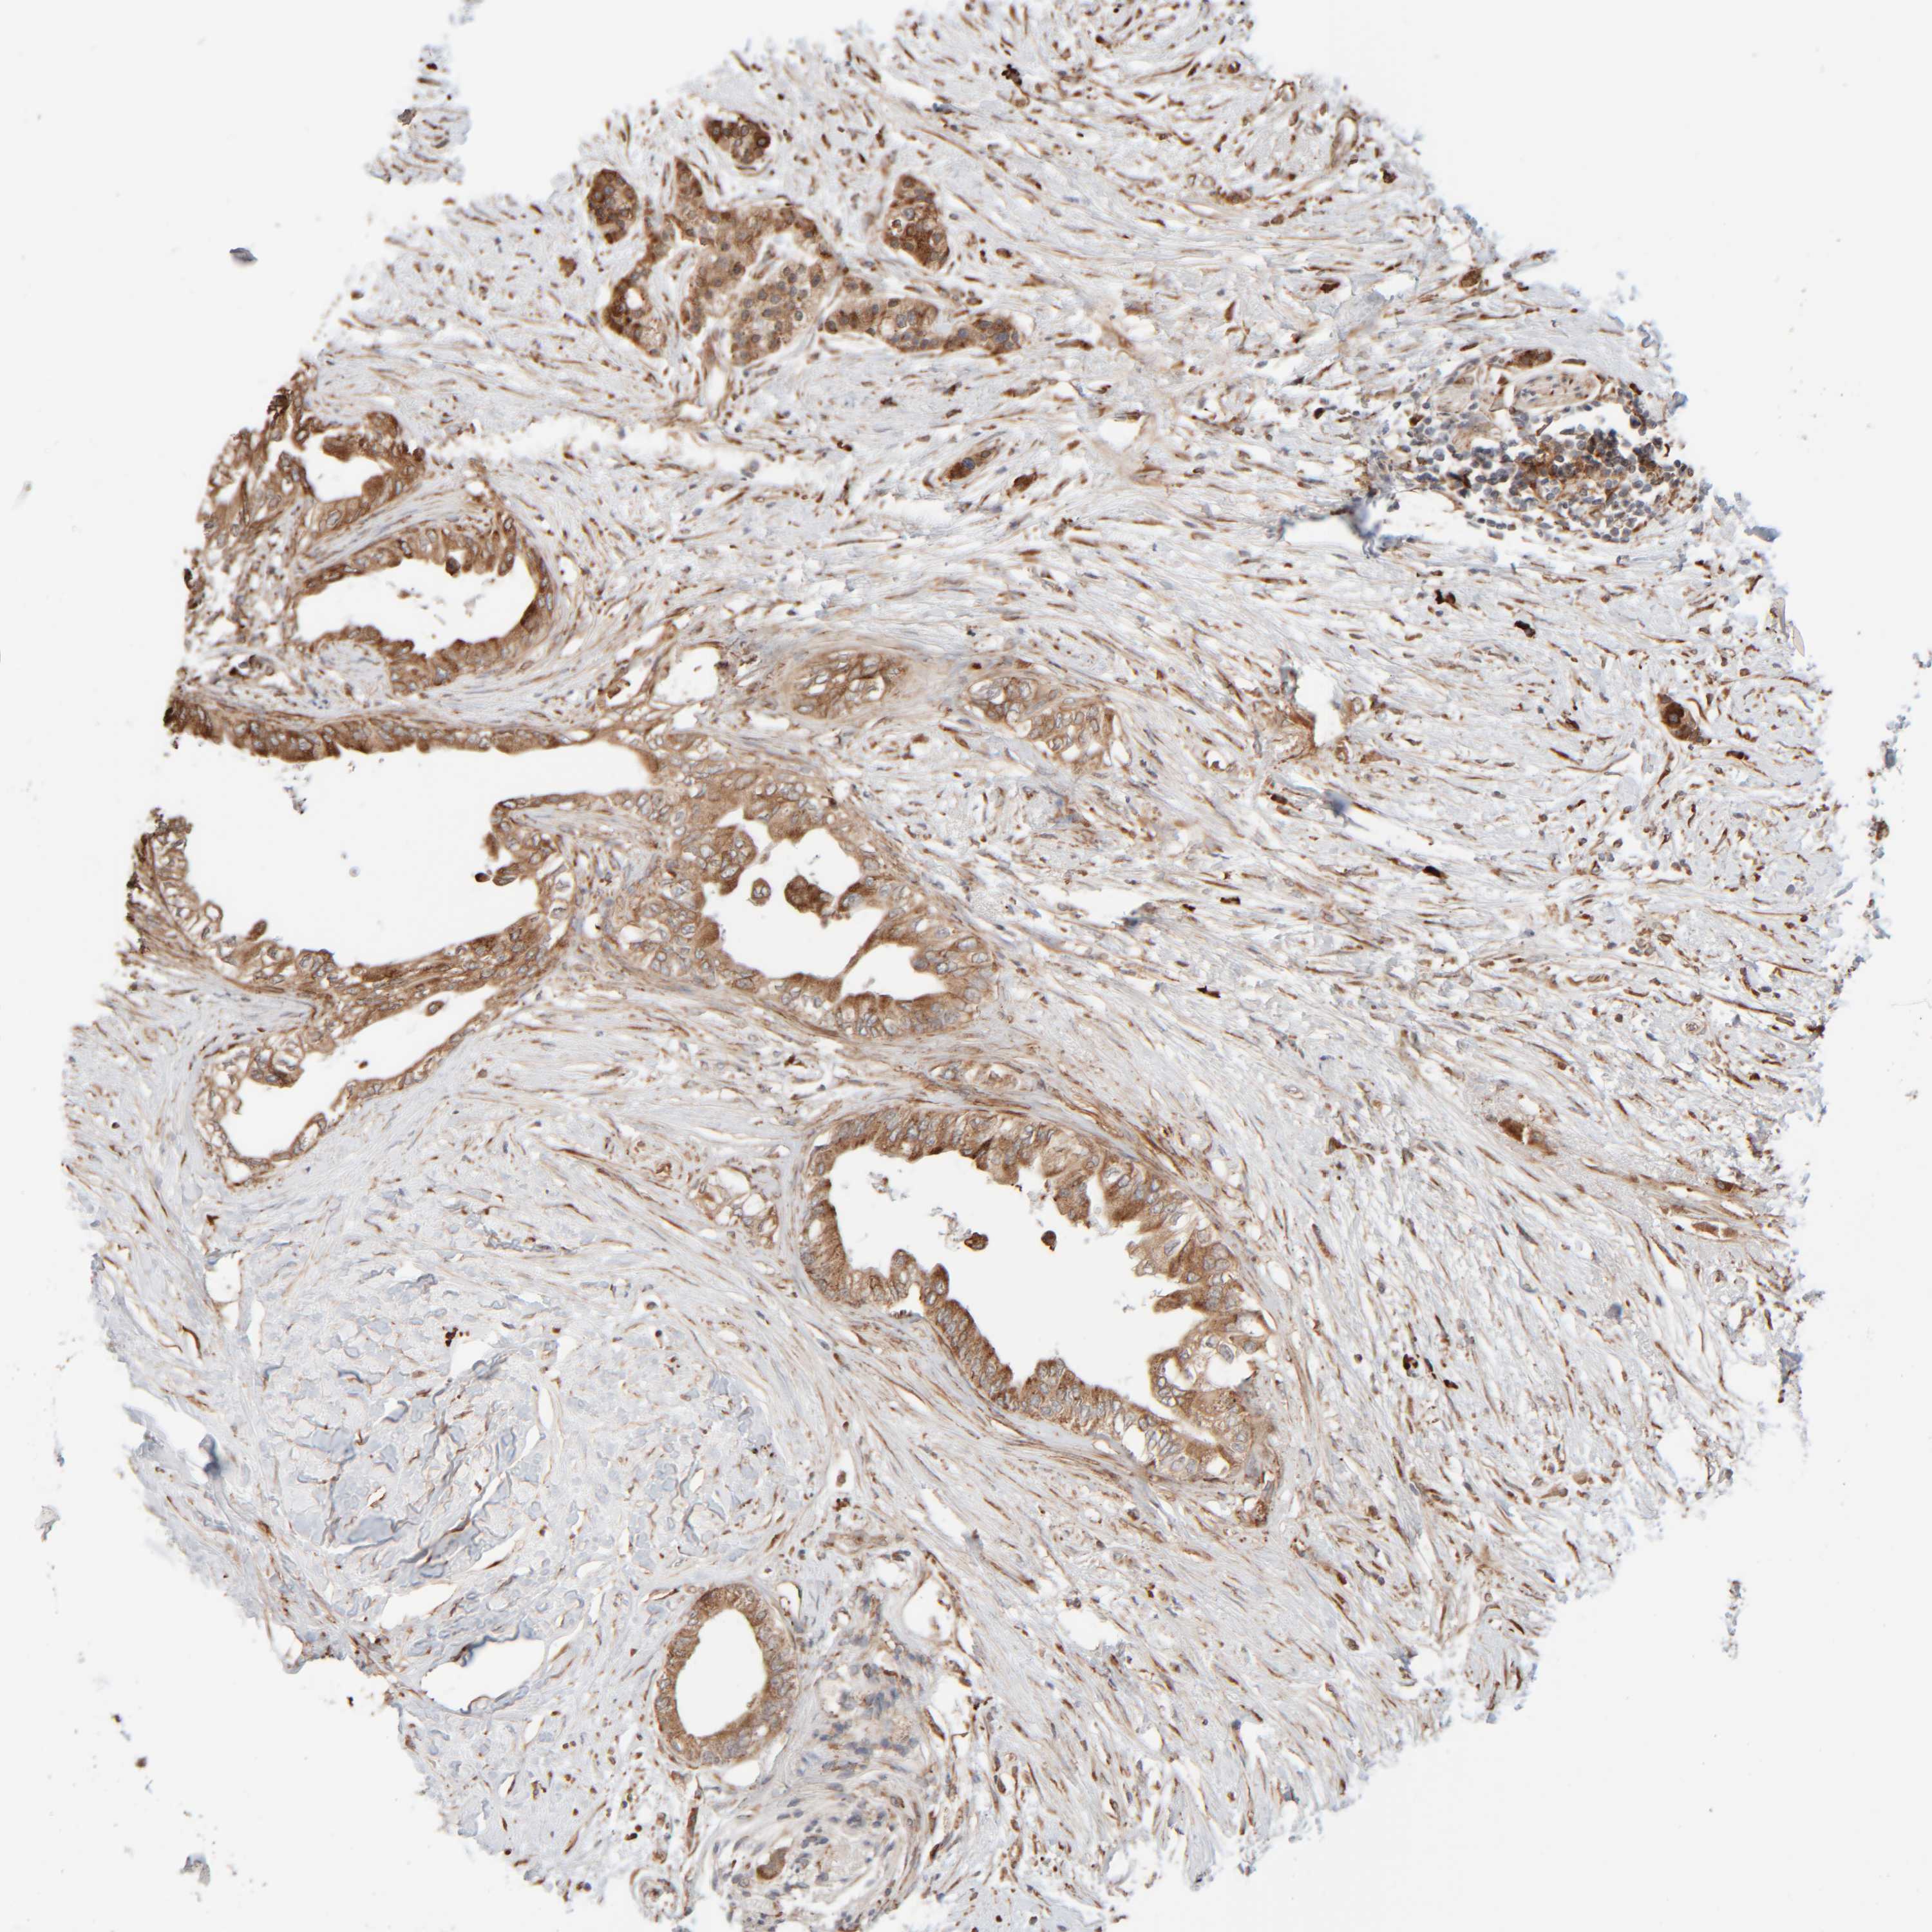

PANCREATIC CANCER - Protein expressioni

A mouse-over function shows sample information and annotation data. Click on an image to view it in a full screen mode. Samples can be filtered based on level of antibody staining by selecting one or several of the following categories: high, medium, low and not detected. The assay and annotation is described here.

Note that samples used for immunohistochemistry by the Human Protein Atlas do not correspond to samples in the TCGA dataset.

Antibody stainingi

Antibody staining in the annotated cell types in the current human tissue is reported as not detected, low, medium, or high, based on conventional immunohistochemistry profiling in selected tissues. This score is based on the combination of the staining intensity and fraction of stained cells.

Each image is clickable and will lead to virtual microscopy that enables deeper exploration of all samples and also displays staining intensity scores, fraction scores and subcellular localization as well as patient and tissue information for each sample.

Antibody HPA021658

Staining

High

Medium

Low

Not detected

Intensity

Strong

Moderate

Weak

Negative

Quantity

>75%

75%-25%

<25%

None

Location

Nuclear

Cytoplasmic/membranous

Cytoplasmic/membranous,nuclear

Adenocarcinoma, NOS